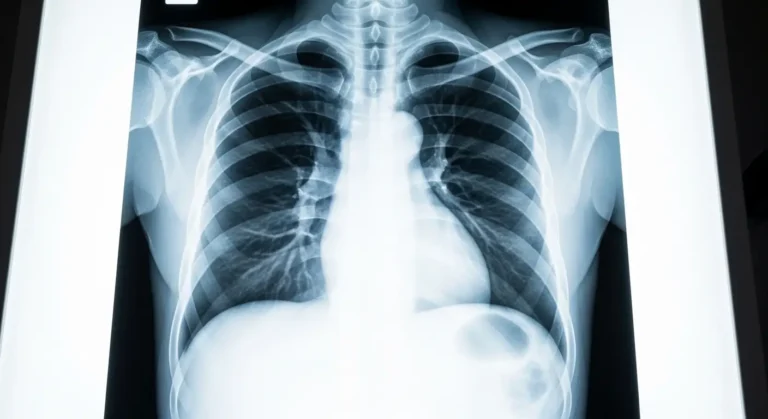

Une radio pulmonaire — appelée aussi radiographie thoracique ou radio des poumons — est un examen d’imagerie médicale qui permet de

visualiser l’intérieur de votre cage thoracique. En quelques secondes, les rayons X traversent votre corps et produisent une image qui montre :

Le radiologue analyse ensuite cette image et rédige un compte rendu qui est transmis à votre médecin traitant. C’est lui qui vous expliquera les résultats et décidera des suites à donner.

Sur une radio pulmonaire normale, voici ce que le radiologue observe :